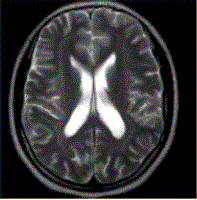

问题 女性,21岁,部分性癫痫,MR表现如下图,可能的诊断是

选项 A.神经纤维瘤病I型 B.神经纤维瘤病II型 C.结节性硬化 D.带状型灰质异位 E.颜面血管瘤综合征

答案 D